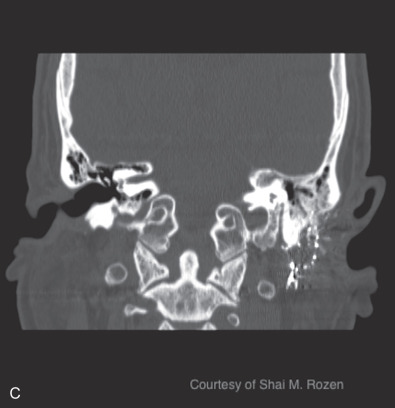

Temporal bone fractures are a product of high-energy blunt trauma commonly resulting in fracture, hemorrhage, nerve trauma, vascular damage, with disruption of the middle or inner ear structures, classically classified into longitudinal, transverse, or oblique fractures. Longitudinal fractures often result from lateral to medial forces extending through the facial nerve canal, possibly causing intraneural hemorrhage, transection, or bone compression. They can disrupt the ossicular chain, resulting in conductive hearing loss. Transverse fractures often result from anterior posterior forces with a fracture line often traversing the vestibulocochlear apparatus causing sensorineural hearing loss and equilibrium disorders. Transverse fractures more commonly injure the facial nerve due to proximity to the nerve’s labyrinthine segment. Oblique, also termed mixed, fractures include both longitudinal and transverse components. Additional classifications are based on degree of involvement of the petrous portion of the temporal bone, or the otic capsule. Temporal bone computed tomography (CT) scans should be performed in thin-section 1 mm cuts to avoid interpreting normal suture lines as fractures.

Blunt injuries resulting in temporal bone fractures are often encountered in motor vehicle accidents, altercations, or falls from heights. Approximately 7%–10% of temporal bone fractures result in facial nerve injury. Temporal bone fractures have several classifications. Fracture line orientation relative to the petrous bone defines fractures as longitudinal (70%–80%), transverse (10%–20%), and oblique (10%). Facial paralysis occurs most commonly in transverse fractures (50%) but may also occur in longitudinal fractures (25%). More modern CT-based classifications assess whether fractures are otic capsule sparing or violating, the latter being twice as likely to cause facial paralysis. Four types of facial nerve trauma have been found in temporal bone fractures. In 76% of longitudinal fractures either bony impingement or intraneural hematoma was found, and in 15% the nerve was transected. In the remainder of patients, no visible pathology was found other than neural edema. In transverse fractures, 92% were transected and 8% had impingement ( Fig. 1.5.3 ). Similar to penetrating intracranial facial nerve injuries, surviving patients are initially often in critical condition and the facial paralysis is often unnoticed.